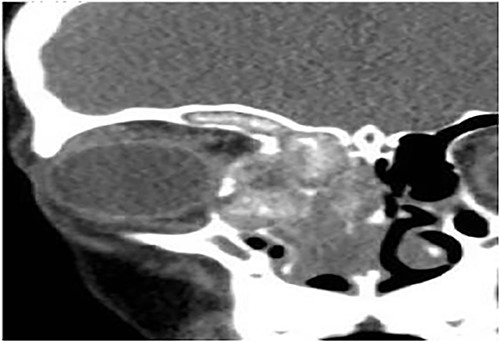

Case 6 (extensive into intraorbital and intracranial structures)

A 15-years-old male presented with bilateral nasal obstruction for a long time associated with nasal discharge, allergic nasal symptoms and headache. Endoscopic nasal examination revealed bilateral extensive nasal polyposis and mucin. CT scan (Fig. 7) and magnetic resonance imaging (MRI) scan (Fig. 8) of the paranasal sinuses confirmed the diagnosis of extensive bilateral allergic fungal pansinusitis with intraorbital and intracranial extradural extension. The patient underwent FESS, and all the polyps, mucin and fungal debris were removed from the sinuses. The patient continued on medical treatment and remained symptoms-free for 5 years follow-up.

Coronal CT paranasal sinuses shows heterogeneous opacities of the ethmoid and maxillary sinuses bilaterally. It is associated with complete opacification and extension through the widened ostiomeatal complex, obliterating the nasal cavities with polyposis. The ethmoid sinuses show expansion with lateral displacement and partial dehiscence of the lamina papyracea bilaterally. The roof of the right ethmoid sinus shows dehiscence with intracranial extension.

Sagittal T1 post contrast MRI paranasal sinuses shows expansion of the frontal sinus and anterior ethmoid with intracranial extension limited by the dura. The sphenoid sinus shows complete opacification and expansion displacing the pituitary fossa superiorly. The nasal cavity is obliterated by nasal polyposis.